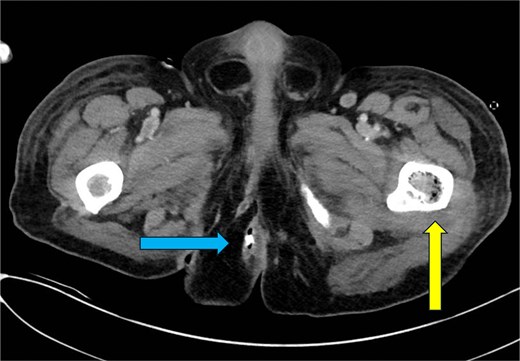

CT abdomen and pelvis—axial plane. Intraosseous gas is seen in the left femur at roughly the level of the lesser trochanter (yellow arrow, right). A previously drained perianal abscess (blue arrow, left).